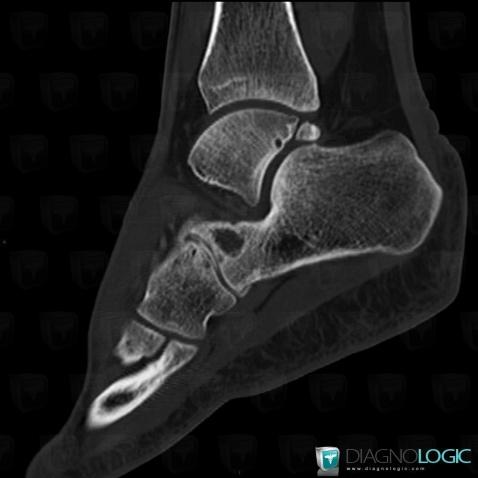

Here is the specific information in the key image above:

- Diagnosis Degenerative joint disease, Location(s) Calcaneus, with gamuts Lucent lesion in foot, Sclerotic lesion in footMid tarsal joints, with gamuts Monoarticular joint disease